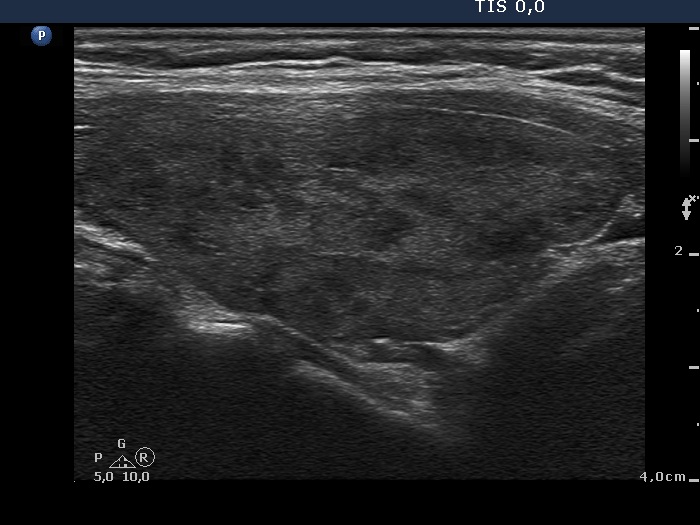

Differentiation of discrete lesions - case 1225 (ultrasonographic picture 5)

Right lobe, longitudinal scan